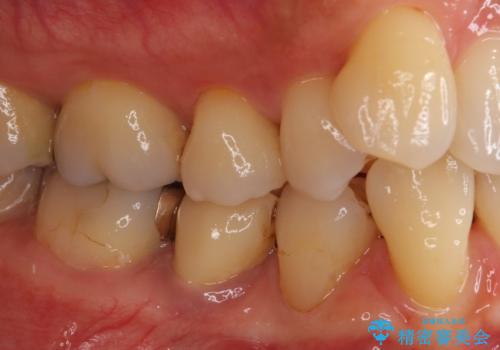

歯に穴があいた 奥歯のセラミック治療

虫歯を全て除去したうえで新しい土台を築製し、セラミッククラウンにより補綴治療を行うこととしました。

虫歯が歯根深くまで及んでいる場合には歯を部分矯正で引っ張り出したり、歯周外科処置が必要となったりしますが、メインテナンスでレントゲン写真を定期的に撮っていたため、幸いにも矯正や外科処置が必要となる前に補綴治療を行うことができました。